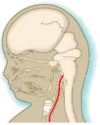

Where is the head, neck and face at by early week 4?

- The neural tube forms in week 3

- By week 4, the embryo has folded (creating primitive gut tube, including primitive pharynx)

- By early week 4 = no distinguishing features on face, but there is a head and neck

- It takes up approx 1/2 length of the embryo

Note: the image is d22